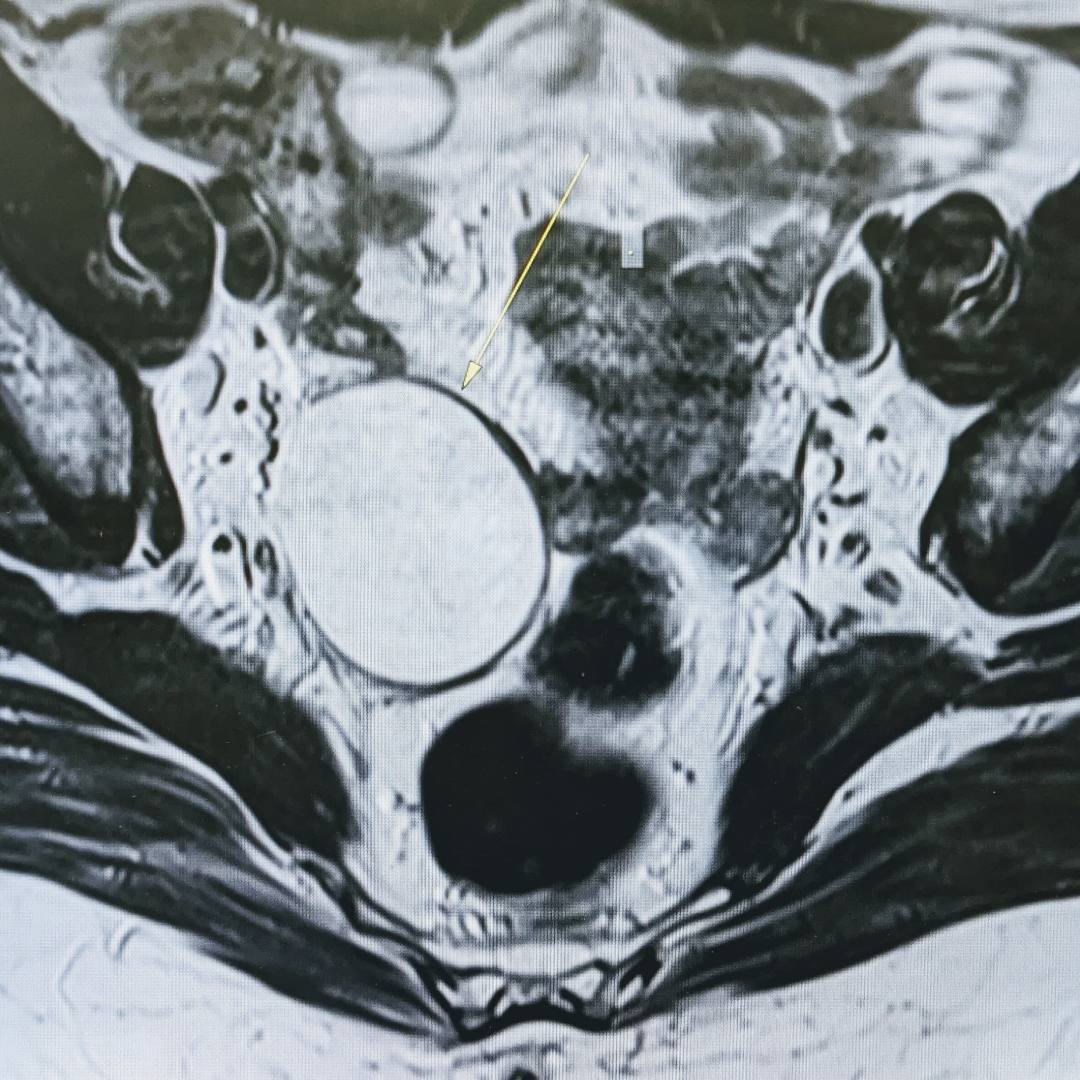

53-летняя пациентка обратилась к гинекологу в рамках программы check-up. При осмотре документации выяснилось, что на проведенных УЗИ-исследованиях от 2021 и 2023 года определяется образование правого яичника, требующее дифференциальной диагностики между эндометриоидной кистой и кистозно измененным яичником.

С целью оценки образования, уточнения его структуры и динамики роста пациентке было проведено МРТ органов малого таза.

При МРТ было выявлено жидкостное кистозное образование правого яичника без папиллярных разрастаний, гораздо больших размеров относительно первоначального УЗИ-исследования.

Учитывая анамнез пациентки, особенности структуры и размеры образования, была заподозрена цистаденома.